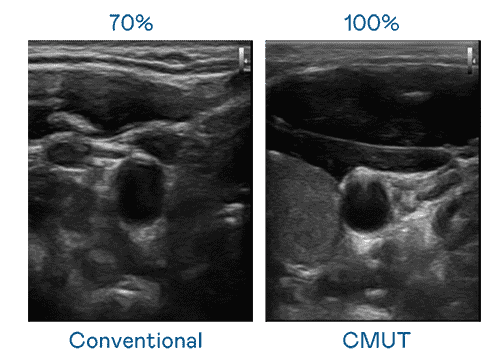

CMUT 技术是一种用电容式微机电元件来产生超音波讯号的技术。。。。与传统 PZT 压电式技术相比,,,,CMUT 频宽增加 30%,,,更宽频的超音波讯号让影像解析度大幅提升,,是实现高影像品质医疗超音波扫描、、促进精准医疗发展的关键技术。。。

大频宽带来超清晰影像

超音波影像的解析度高低,,,,首先取决于探头能发出的讯号频宽。。。万利 CMUT 可提供高清晰的超音波讯号,,,提供高频宽、、高灵敏度、、、、影像纹理细节更高的超音波影像,,,,协助医护人员缩短影像判读时间及利用精准的医疗影像进行诊断。。。。